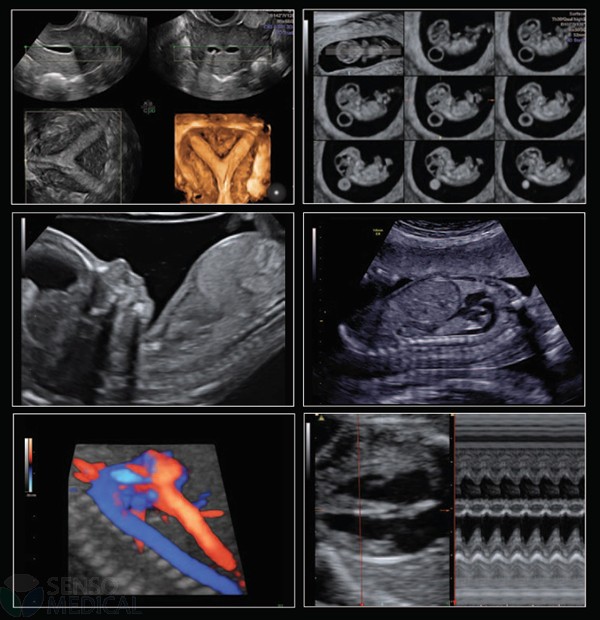

Ultrasonograf GE Voluson E8 Expert wersja oprogramowania BT13 (UISApp 13.0.6.254) 4D HDLive –

System Voluson E8 Expert to unikalne rozwiązanie w zakresie diagnostyki chorób kobiecych oferujące wysoką jakość obrazowania w trybach 2D i 3D/4D oraz uproszczone procedury usprawniające przepływ pracy i zapewniające najwyższą jakość badań. Więcej szczegółów, mniej wysiłku!

Oprócz najnowocześniejszych opcji obrazowania w usg 2D 3D 4D oraz opcji dopplerowskich posiada także funkcję ELASTOGRAFII.